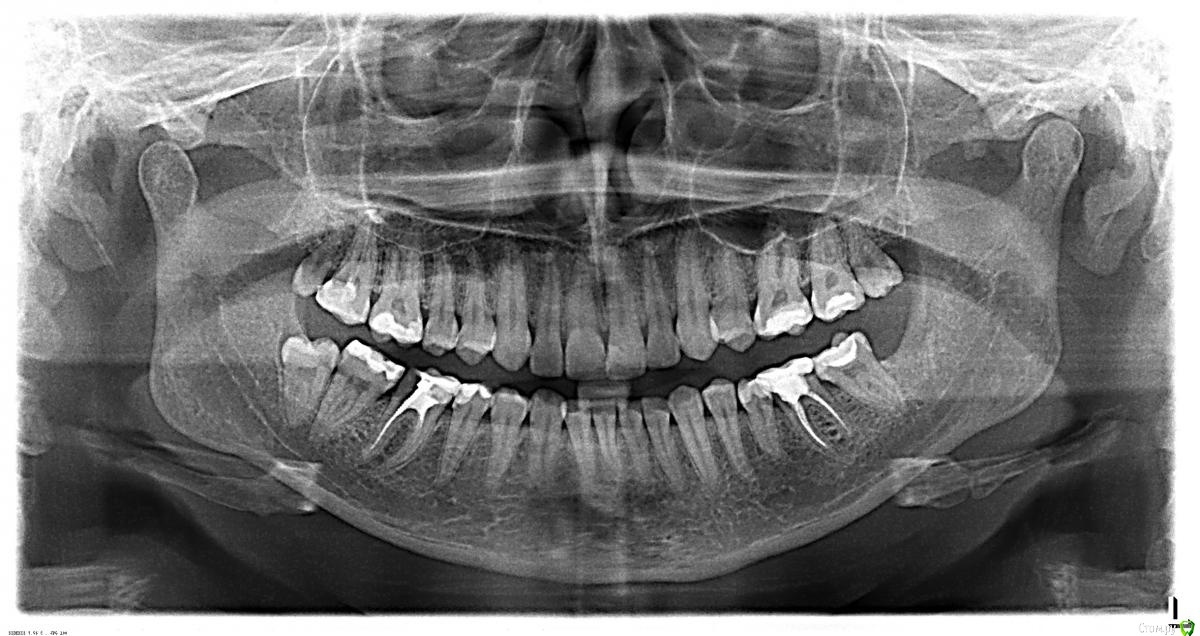

vovovna Опубликовано 21 января, 2015 Поделиться Опубликовано 21 января, 2015 Добрый день, Есть ли возможность по панорамному снимку определить, какие зубы требуют протезирования, а заодно и другого лечения? Сходила на консультацию в клинику рядом с домом (т.е. врачей не знаю совершенно, отзывов предварительно не читала, мнения о них не имею), заодно впала в печаль по поводу рекомендации протезировать 8 зубов. Более того, на верхней правой 6 (которая в настоящее время болит) речь идет об удалении нервов (что не вызывает вопросов), но рядом стоящая 7 была "пролечена" летом с удалением нерва. По ней сказали, что удален 1 нерв из 4, плюс остатки инструмента, говорят, в несчастном пролеченном канале. Естественно, на перелечивание. В довершение, настоятельно рекомендуется ортодонтическое лечение (о чем я наслышана давно, но все откладываю принятие решения по нему). Что бы вы сказали своему близкому родственнику по данному вопросу - надо? Можете ли вы как-то прокомментировать такой план лечения. Спасибо Ссылка на комментарий

AlexanderGudkov Опубликовано 21 января, 2015 Поделиться Опубликовано 21 января, 2015 (изменено) Родственнику я бы посоветовал:16 - пломбирование каналов + коронка (если при осмотре выяснится, что это необходимо)17,46 - перелечивание + коронки36 - коронка (предварительно посмотреть в каналы)Удалить оставшиеся зубы мудростиОртодонтия. Остальное по этому снимку плоховато видно, после очного осмотра и прицельных снимков еще что-то может потребовать лечения Изменено 21 января, 2015 пользователем AlexanderGudkov Ссылка на комментарий

Romanson Опубликовано 21 января, 2015 Поделиться Опубликовано 21 января, 2015 Насчет болей нужно более детально диагностировать, какой именно зуб дает симптомы. Вполне вероятно, что болит семерка, т.к. судя по снимку пролечена она неважно. Насчет коронок - вероятно, вам их рекомендовали как замену пломбам. Тут нужно смотреть на состоятельность пломб, если их краевое прилегание не нарушено, сколов пломбировочного материала нет - то можно и не короновать. Из проблемных зубов, которые видно по снимку - это две нижние шестерки и левая верхняя семерка, которые точно требуют ортопедической конструкции, причем шестерка, которая слева (на снимке) нуждается в повторном эндодонтическом лечении как и верхняя левая семерка. Ещё возможна проблема в верхней правой и нижней левой семерках, по снимку похоже на вторичный кариес под пломбой. Ссылка на комментарий